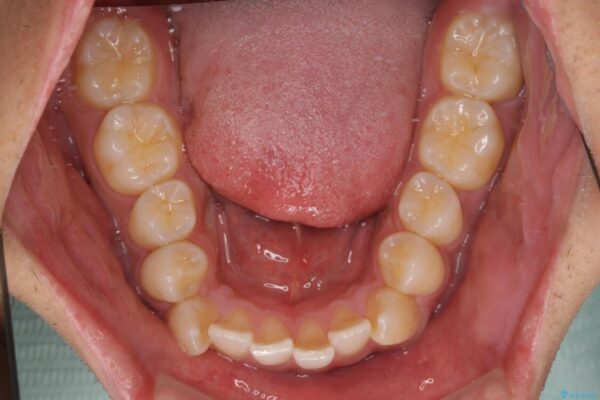

治療後

• 八重歯と前歯のガタガタを抜歯矯正で治療|クリアブラケット使用例 治療後画像

八重歯はきれいに整い、前歯もバランスよく収まり、横顔のラインも自然に改善されました。

治療後、患者様は「思い切り笑えるようになった」と大変喜んでくださいました。